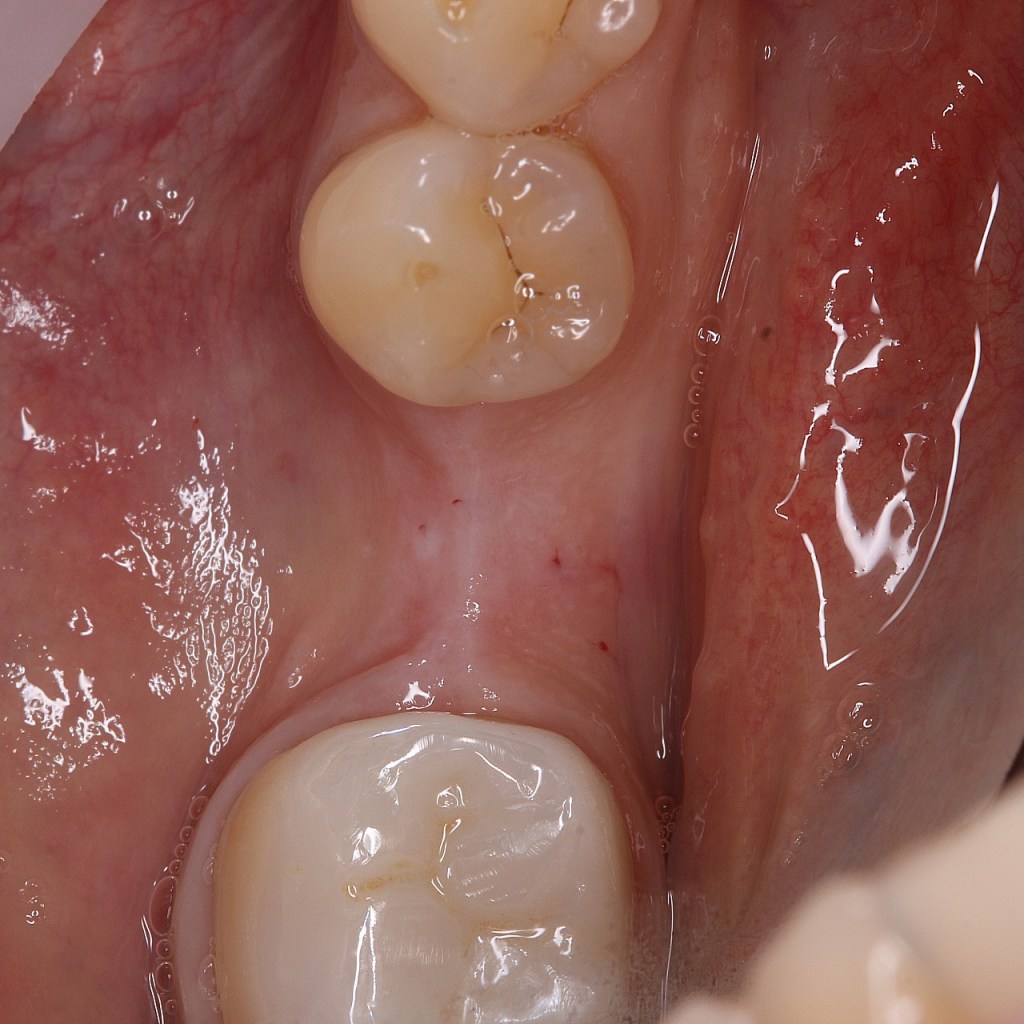

Implant Megagen Anyridge, inserat intr-o creasta atrofica, de 6,5mm latime. Simple anyridge implant placement, with bone expansion and CTG to compensate the 6,5mm bone crest.

Insufficient crest width and thin tissue